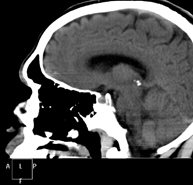

- Skull CT

Radiological test that provides high definition anatomical images of the skull (brain stem, cerebellum, cerebrum, cranial calotte, etc.) using CT (Computed Tomography) equipment. Indicated for: trauma, headache, memory disorders, sudden loss of strength in a limb or half of the body.